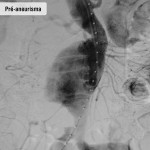

Fotos